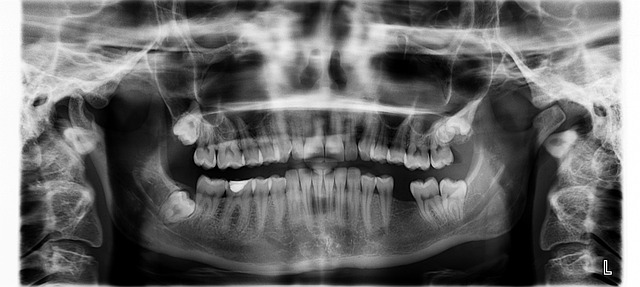

치아 교정의 첫 단계는 문제를 파악하고 필요한 치료를 결정하는 임상 검사입니다.

이를 위해 얼굴과 입안 사진 촬영, 본뜨기, 엑스레이 촬영, 성장 검사 등이 필요합니다. 이러한 자료는 정확한 진단을 위한 중요한 기초가 됩니다.